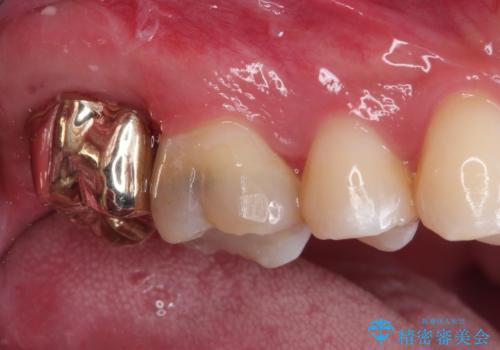

歯肉に埋もれたマージンライン 奥歯の被せもの

- 被せものが取れたことを主訴に来院されました。

以前の被せもののマージンは歯肉縁下に深く形成され、根尖病変も認めたため、根管治療(林先生に依頼)、歯周外科、PGAクラウンにて修復治療を行いました。